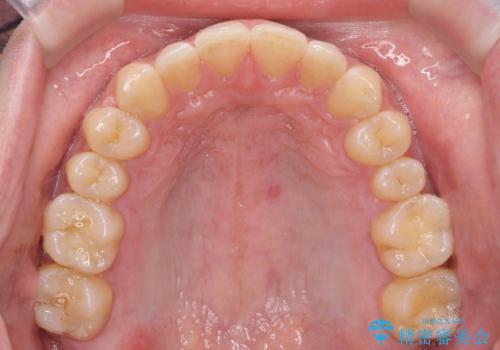

時間はかかるが矯正治療で天然の歯の隙間をつめて歯を削らなくて済むというご案内をしたところ、セラミックでかぶせるのはやめて、矯正治療を行うことになりました。

ただし矯正を選択した場合は、治療後またすき間があかないように保定が必要になります。

それぞれ特徴がありますので十分お考えの上選んでいただき、治療結果には満足していただけたと思います。

インビザライン(マウスピース矯正)は小さな隙間を閉じるのは得意です。

また、隙間を閉じる方法は矯正が一番いいわけではなく、矯正治療、セラミック治療それぞれ特徴があります。

当院では両治療のメリットデメリットを説明した上で選んでいただくことが可能です。